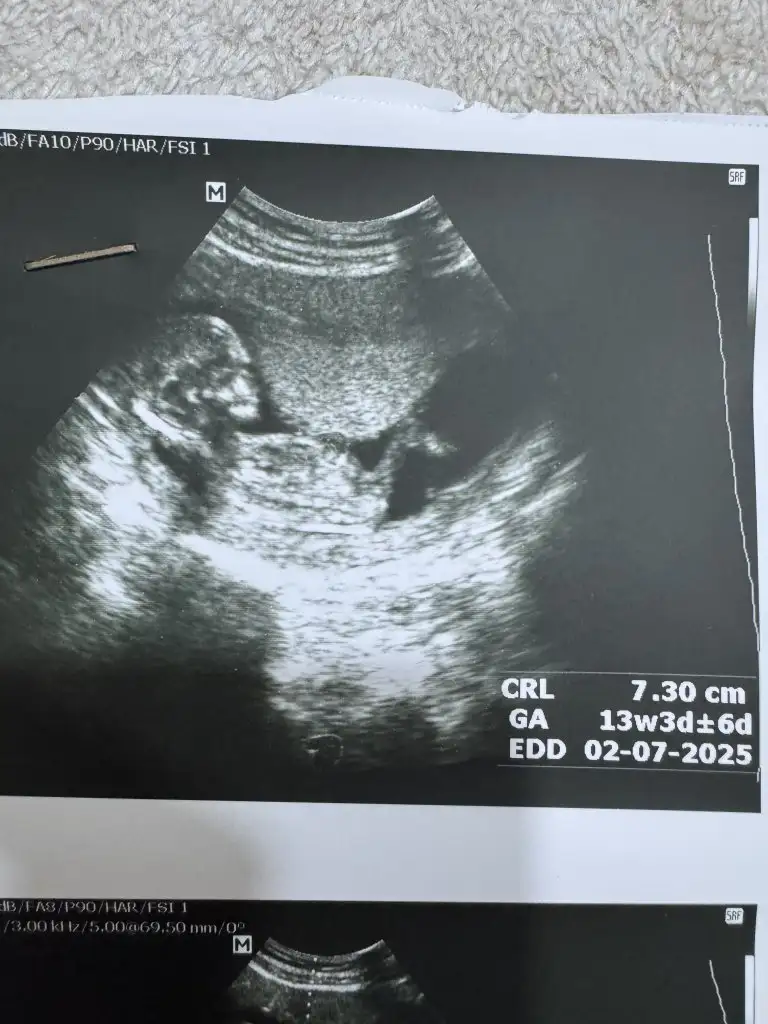

Erkek :) mezhanesi yukardaBanada cinsiyet tahmini yapabilcek var mı doktorum bi tahminde bulundu ama 12+5 haftaligiz

Merhaba benimde burda 12 hafta 5 gün bu haftalarda bacak arası sizdemi böylemiydi? Doktor erkeğe benziyor kızda ola bilir söyledi. Merak ediyorum böyle kız bebek genital organı olurmu?Bana da erkek dediler iki bacak arası diyor net bence

Benimde bacakmarası böyleydi erkek dediler ondan önceki bu posta attığım resimde 12+0 da %90 kız demişti hatta ebe de benim gibi bacak arasına bakarak evet hocam bende görüyorum bu cıkıntıyı demişti doktor yine bakıyorum ben kız diyorum dedi sonra erkek dendi katışık yani bacak arası resmi yok maalesef görüntü resim vermiyorlar cekemedimMerhaba benimde burda 12 hafta 5 gün bu haftalarda bacak arası sizdemi böylemiydi? Doktor erkeğe benziyor kızda ola bilir söyledi. Merak ediyorum böyle kız bebek genital organı olurmu?

Kızlarda da çıkıtı oluyor ama benim bildiğim farklı sivri üçken şeklinde.Bazen erkeklerde küçük oluyor.Fazlasıyla dr. Silvio Omori videoları izledim kafam karıştı artı. Önemli olan sağlıklı olması tabiki bir cinsiyet arzum yok oğlumda kızımda var, burda cinsiyet öğrenmek çok zor söylemiyorlarBenimde bacakmarası böyleydi erkek dediler ondan önceki bu posta attığım resimde 12+0 da %90 kız demişti hatta ebe de benim gibi bacak arasına bakarak evet hocam bende görüyorum bu cıkıntıyı demişti doktor yine bakıyorum ben kız diyorum dedi sonra erkek dendi katışık yani bacak arası resmi yok maalesef görüntü resim vermiyorlar cekemedim